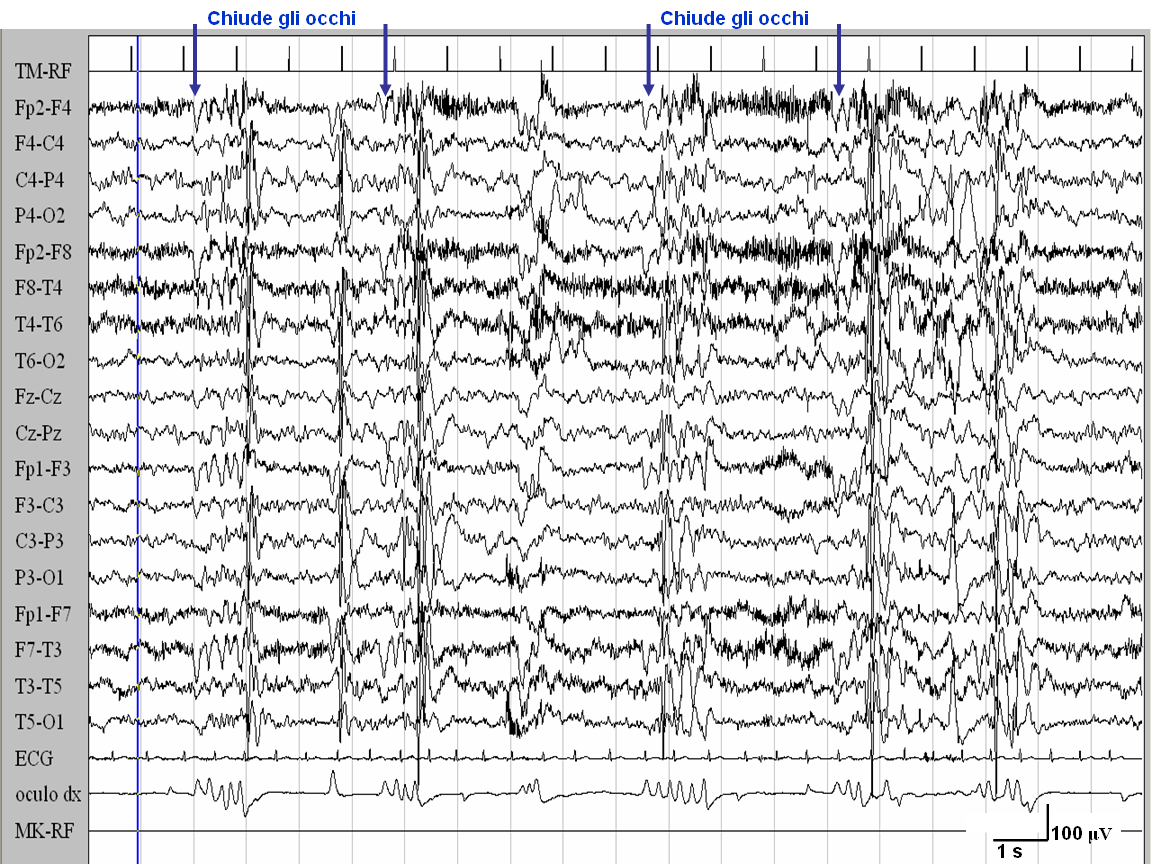

È

stato effettuato uno studio EEG standard con registrazione Video-EEG

in veglia in presenza di normale luce ambientale: in entrambi i casi

entro 1 secondo dalla chiusura degli occhi sono comparse scariche

generalizzate di punta-onde, di durata inferiore ai 3 secondi, a cui

si associa clinicamente il fenomeno motorio della mioclonia

palpebrale. In entrambi i soggetti la chiusura degli occhi in

presenza di oscurità ambientale non ha provocato alcuna

scarica EEG, né alcun fenomeno clinico. La stimolazione

luminosa intermittente ha determinato risposta foto-parossistica in

entrambi i casi.

Caso

1. numerose scariche di punte-onde ed onde lente, che compaiono dopo

la chiusura degli occhi